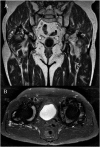

Methods: Ninety-nine patients with 134 hip articulations, 71 MoM THA/RHA and 63 MoP THA participated in a cross-sectional study at XXX University Hospital, Denmark, at mean 7.3 (range: 0.4-21.7) years after surgery. Patients' daily PA was monitored during a two-week period using a triaxial accelerometer. Metal artefact reduction sequence magnetic resonance imaging scans, estimation of serum-ion concentrations of chromium and cobalt and the Copenhagen Hip and Groin Outcome Score (HAGOS) questionnaire were completed on Day 14.

Results: Patients with a pseudotumour who underwent MoM THA/RHA had a higher average cadence of median 101.4 [interquartile range (IQR: 95.5-105)] steps/min than patients without a pseudotumor, median 96.7 (IQR: 92.2-103) steps/min (p = 0.02). Serum-ion concentrations of chromium and cobalt were higher in patients with a pseudotumour who underwent MoM THA/RHA, median 2.57 (IQR: 1.4-3.4) μg/L and 1.80 (IQR: 1.2-2.6) μg/L, respectively, than in patients without a pseudotumour, median 1.85 (IQR: 1.1-3.2) μg/L and 1.34 (IQR: 0.9-2.2) μg/L in MoM THA/RHA (p = 0.04 and p = 0.03). There was no statistical difference in these parameters between patients with and without a pseudotumour who underwent MoP THA. Daily PA levels of patients who underwent MoM THA/RHA were significantly correlated with serum-ion concentrations of chromium (p = 0.0002, r = 0.44) and cobalt (p = 0.005, r = 0.34), whereas no correlations were seen among patients who underwent MoP THA (p > 0.12).